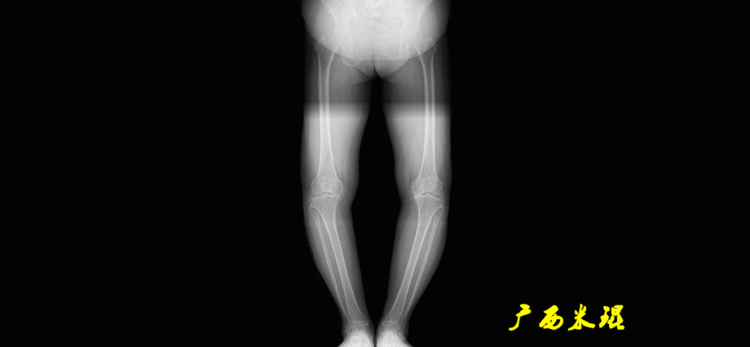

下肢力线及相关角度测量的前提是必须拍摄标准的站立位也就是负重位的下肢全长片。目前这样的照片都是放射科的技师在电脑上拼接出来的,大部分医院的DR都能够做到这一点。

患者直立于摄影架上,后背贴近摄影架,双手自然下垂,膝关节尽量伸直,足部与双肩同宽,要求投照时双髌骨朝正前方,通常患者双足尖应平行向前即可。

提醒一下大家,拍摄过程中应避免下肢的外旋和内旋。如果有一侧肢体短缩时,投照应当用脚垫垫高短缩肢体,使骨盆保持水平,这样下肢短缩测量才精确。如果有肢体旋转畸形时,还是以髌骨朝前为标准,虽然此时双足可能不能保持平行。

最常见的下肢畸形发生于冠状面,即膝内外翻畸形,冠状面的对线异常通过应用“对线异常检验”进行分析,机械轴的偏移(MAD)表现为对线异常。

膝内翻是指下肢力线通过膝关节中心点内侧,距中点2mm以上,偏内超过15mm为显著膝内翻。膝外翻是指下肢力线通过膝关节中心点外侧,距中点2mm以上,偏外超过10mm为显著膝外翻。